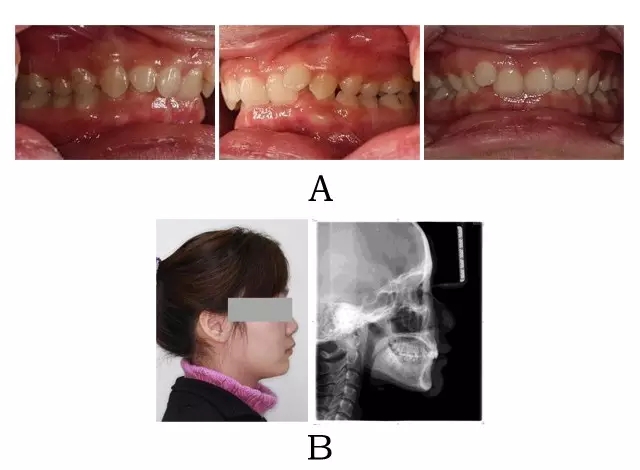

一、臨床表現(xiàn)

面型輕度前突,面下高度不足伴有深頦唇溝??趦?nèi)表現(xiàn)上頜嚴重骨性前突,上前牙過度代償(內(nèi)傾),下頜后退,嚴重深覆合深覆蓋及深 Spee曲線。

圖 4-4:混合 II 型突面畸形臨床表現(xiàn)及頭顱側(cè)位影像特征。

(A)齒槽與牙列特點 (B)側(cè)貌與影像對比

Figure 4-4. Clinical manifestation and cephalometric image for merged skeletal and mandibular positional prognathism (Type II). (A) Alveolar and dentition specifics. (B) Facial profile and radiographic image.